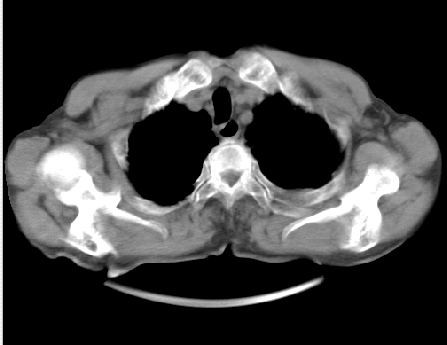

以下是引用hhcckk在2009-5-29 14:58:00的发言:[br]左上周围型肺癌,左肺门、纵隔淋巴结转移,左侧胸腔积液,左侧肋骨转移[br]

以下是引用ct诊断高手在2009-5-29 13:50:00的发言:[br]考虑左侧中央型肺癌,阻塞性肺炎伴肺不张。纵隔淋巴结转移。慢支 肺间质纤维化肺气肿。左侧胸腔积液。左侧肋骨转移?